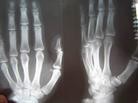

Published on 11/19/2004 		黑龙江双城市付丽被万家劳教所迫害得双手残疾(图)